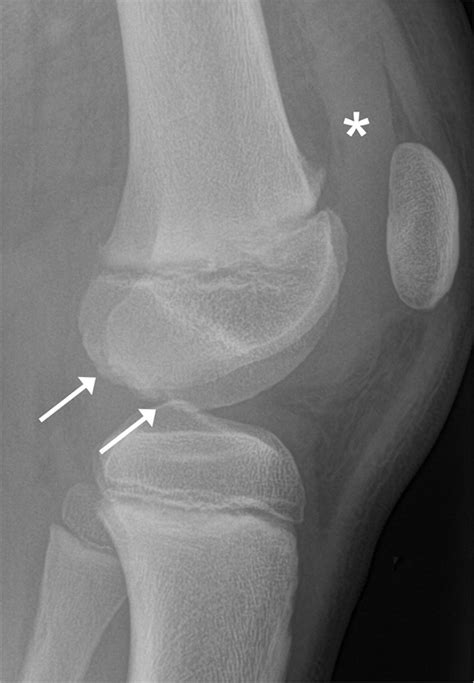

I have an extra bone growth next to my knee that I like to call my

I have an extra bone growth next to my knee that I like to call my ...